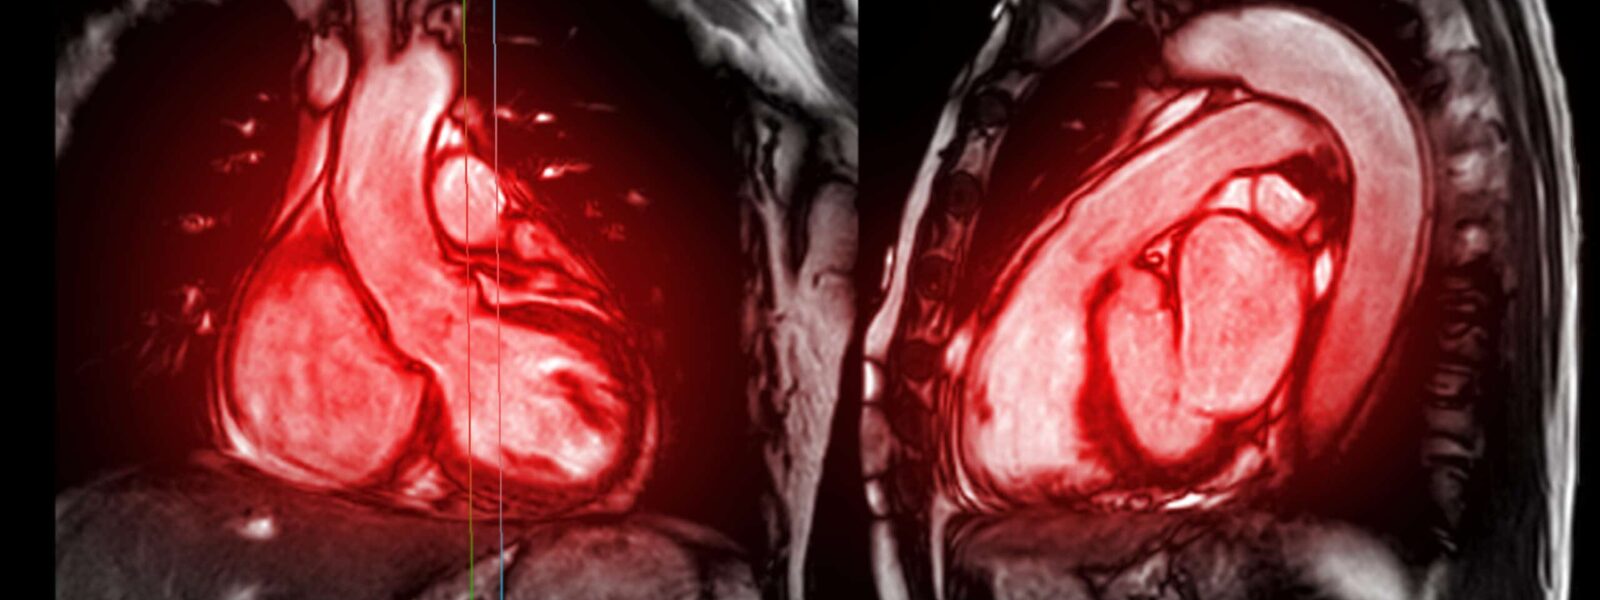

There’s a hidden link between the health of the heart and the brain, scans from more than 40,000 UK Biobank participants suggest.

If the heart appears unhealthy, chances are that this is mirrored by problems in the brain. This heart–brain link was revealed with scans from more than 40,000 UK Biobank participants. It suggests that preventing cardiovascular conditions could also benefit the brain, and hits at a more holistic way in which clinicians could predict someone’s risk of multiple diseases.

Unhealthy changes in the heart are linked to brain structure problems, scans from more than 40,000 UK Biobank participants have revealed. This suggests that preventing heart conditions, or treating them as early as possible, could also keep the brain healthy.

It remains unclear whether these connections are innate or whether the stress of having one medical condition contributes to developing another. To start untangling this question, Zhao and his team analysed more than 80 heart characteristics and more than 450 measures of brain structure and function.

The researchers found, for example, that less healthy heart chambers are linked to poorer ‘wiring’ in the brain. This means the white matter, which connects different parts of the brain, doesn’t appear as it does in a healthy person.